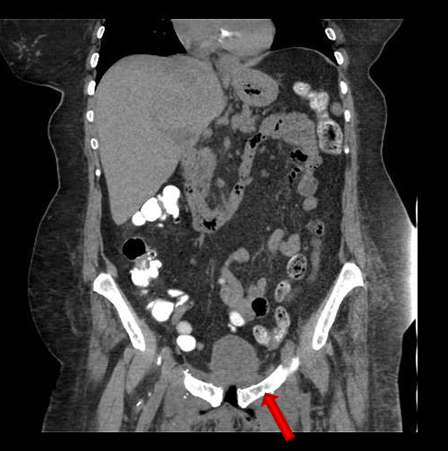

She presented on Emergency room suffering from fever, pelvic pain, and functional impairment of her right lower limb. Physical examination revealed bad smell vaginal flow and loss of strength on her right lower limb. Contrast computerized tomography and magnetic resonance images showed pelvic muscles impairment (Figure 1), inflamed bladder (Figure 2), and pelvic abscess lying from right psoas muscle to pubis bone, which presented radiologic signs of osteomyelitis (Figure 3) and (Figure 4).

Figure 3: CT scan image. Severe osteitis and osteomyelitis signs (cortical and medullary alteration) of bilateral pubic bones.

Share Image: